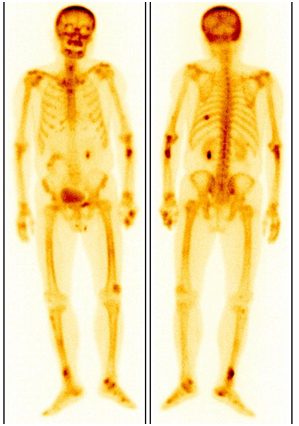

3. 各種代謝性骨病、風(fēng)濕免疫性疾病、骨感染性疾病。

老年男性,因骨痛外院檢查發(fā)現(xiàn)骨質(zhì)破壞,考慮“骨轉(zhuǎn)移”來診。ECT顯示四肢多發(fā)局灶性代謝增高灶并有“黑顱征”,診斷為甲狀旁腺功能亢進性骨病。